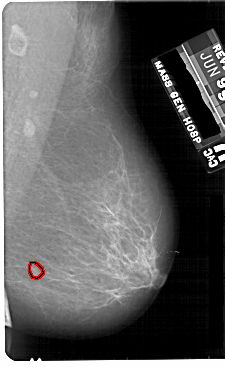

A_1816_1.LEFT_MLO

LEFT_MLO LINES 5491 PIXELS_PER_LINE 3466 BITS_PER_PIXEL 12 RESOLUTION 43.5 NON_OVERLAY

FILE: A_1816_1.RIGHT_MLO.OVERLAY

TOTAL_ABNORMALITIES 1

ABNORMALITY 1

LESION_TYPE MASS SHAPE IRREGULAR MARGINS ILL_DEFINED

LESION_TYPE CALCIFICATION TYPE PUNCTATE DISTRIBUTION CLUSTERED

ASSESSMENT 4

SUBTLETY 2

PATHOLOGY MALIGNANT

TOTAL_OUTLINES 1

BOUNDARY